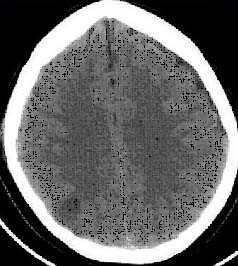

б) Признаки эпидуральной гематомы на КТ и МРТ. Эпидуральная гематома (ЭДГ) представляет собой скопление крови между черепом и твердой мозговой оболочкой, как правило, артериального происхождения и редко из вены / синуса ТМО.

Ключевые данные визуализации:

- Двояковыпуклая (чечевицеобразная) масса (скопление) повышенной плотности между костью и мозгом.

- Смещение ткани мозга.

- Ограничена швами, лишь изредка пересекая их.

- Может пересекать среднюю линию.

- Два последних пункта облегчают дифференциальную диагностику с субдуральной гематомой.

- Обычно односторонняя (95%) и супратенториальная (95%), а также связанная с локализацией перелома (90%).